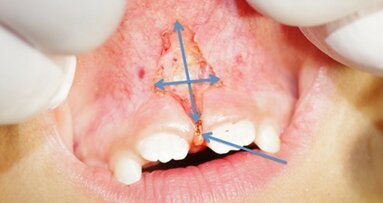

J'ai récemment reçu un e-mail, d'un dentiste généraliste, avec l'image de la dent 27 (image 1). Le mail : "j'ai une radiographie du traitement de canal radiculaire de la 27 de notre fils, fait, il y a cinq ans, par un endodontiste. Il a mal. Je voudrais votre avis sur la ré-intervention ?" Il n'y avait aucune information supplémentaire.

Figure 1_Cas Clinique case (dent 27).

Figures 4a et b_Retraitement d'un traitement de canal radiculaire échoué utilisant les concepts et les stratégies discutées dans l'article.